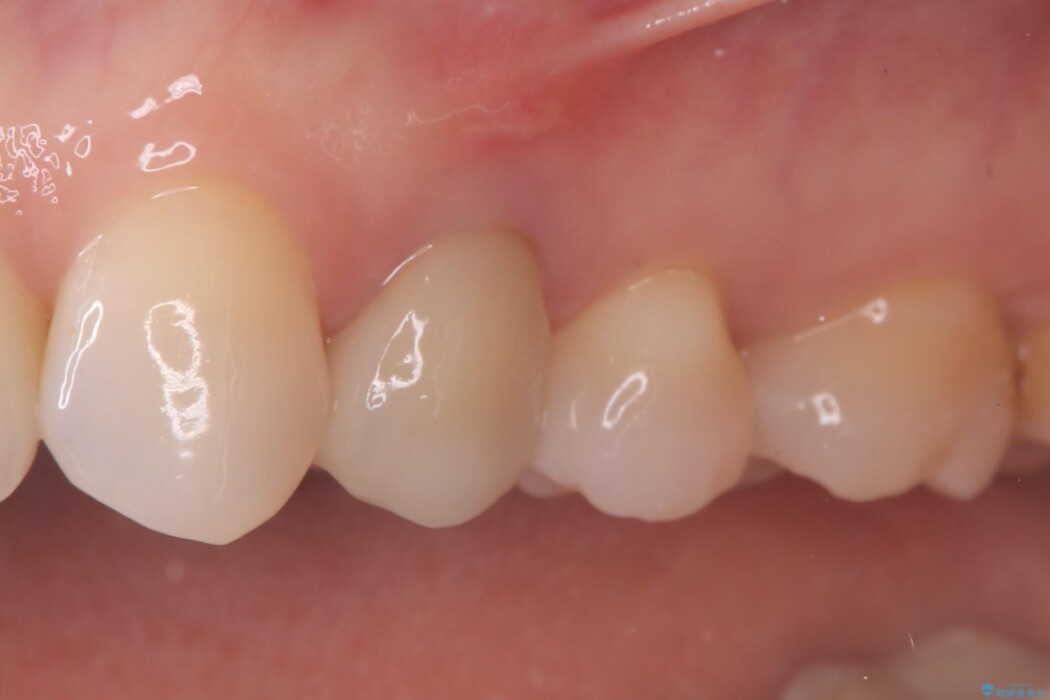

被せ物を除去し、マイクロスコープにて内部を強拡大で確認したところ、歯の根の深い位置まで真っ直ぐにひびが入っていることを確認し、保存が不可能な状態であったため抜歯をすることとなりました。

インプラント治療後は「長年悩まされた痛みから解放され、自分の歯と同じように食事ができるようになった」と喜んでいただけました。